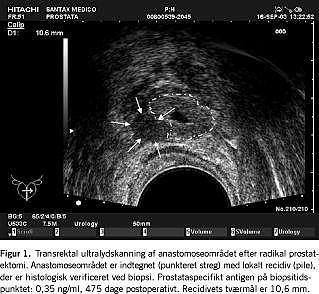

Da PSA-værdierne er relateret til tumormængden, er lave PSA-værdier relateret til små tumorvolumina. Billeddiagnostiske metoder har derfor ofte kun begrænset anvendelse. Det kan dog være muligt f.eks. ved transrektal ultralydskanning (TRUS) at se recidiv i anastomosen imellem blære og urethra (Figur 1 ). Diagnosen kan biopsiverificeres histologisk. Negative fund ved TRUS eller negative fund ved systematiske biopsier fra anastomoseområdet udelukker dog ikke tilstedeværelsen af lokalrecidiv.